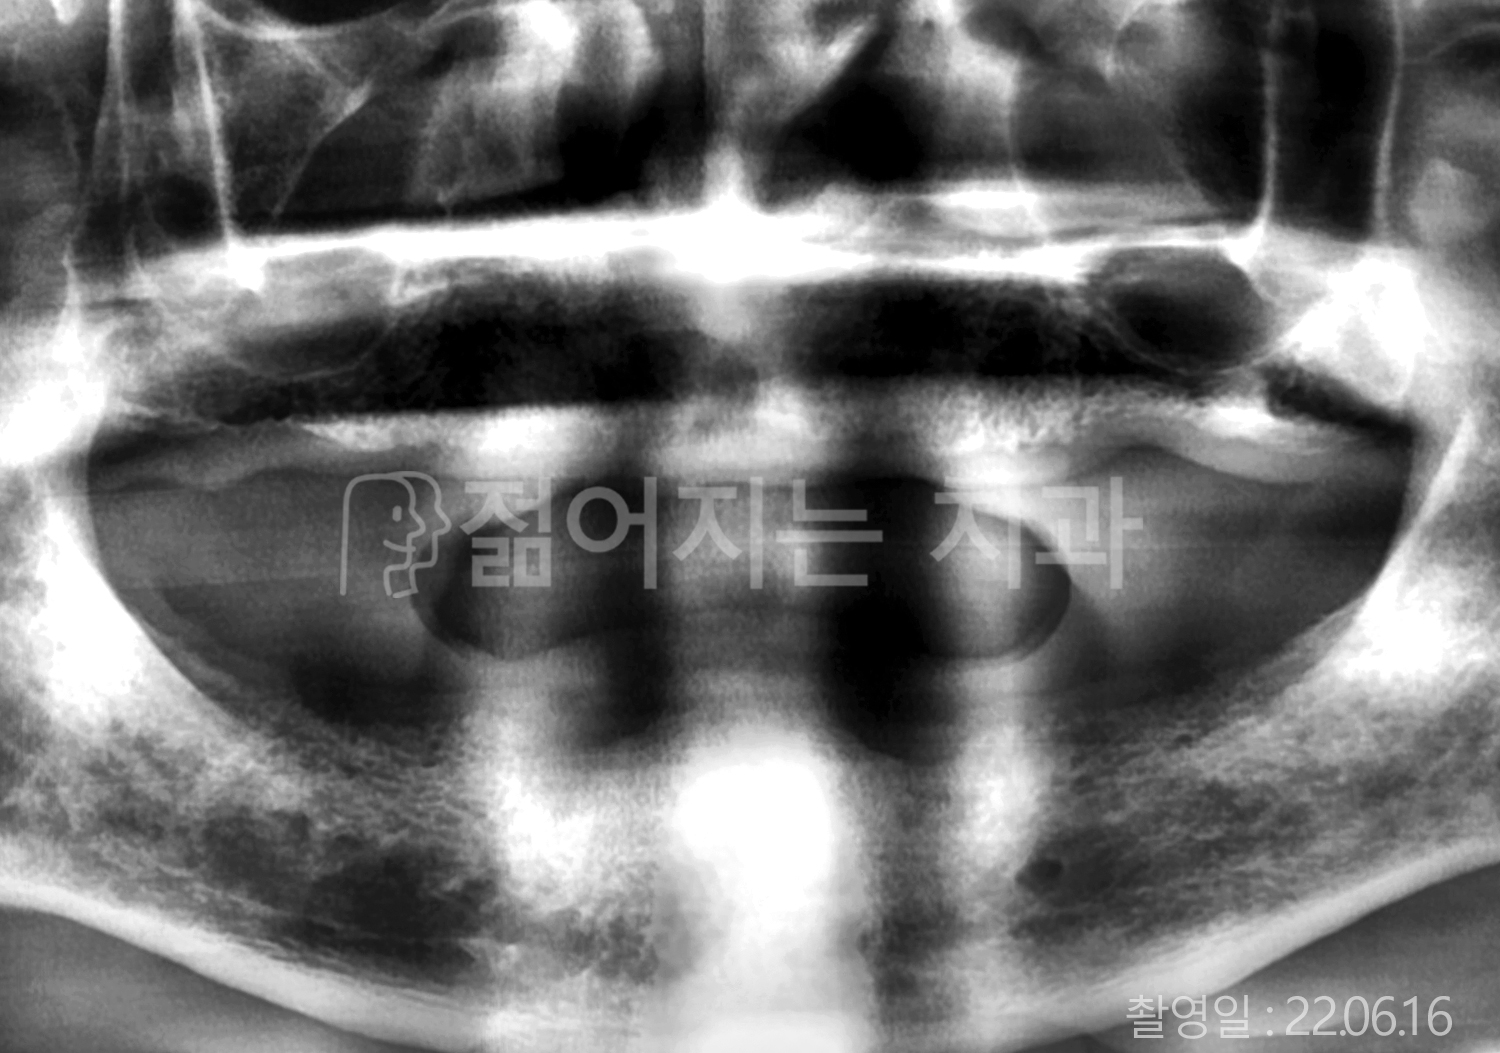

• 70대 고혈압, 고지혈증 전체치아 10개 이상 임플란트

• 60대 당뇨, 간염 전체치아 10개 이상 임플란트

• 80대 골다골증 전체치아 6개 이상 임플란트

• 70대 고혈압, 당뇨 전체치아 10개 이상 임플란트

• 60대 간 질환 전체치아 10개 이상 임플란트

• 60대 전체치아 10개 이상 임플란트

• 70대 전체치아 10개 이상 임플란트

• 50대 전체치아 10개 이상 임플란트

• 60대 고혈압, 고지혈증 전체치아 10개 이상 임플란트

• 40대 고지혈증, 뇌혈관 질환 전체치아 10개 이상 임플란트